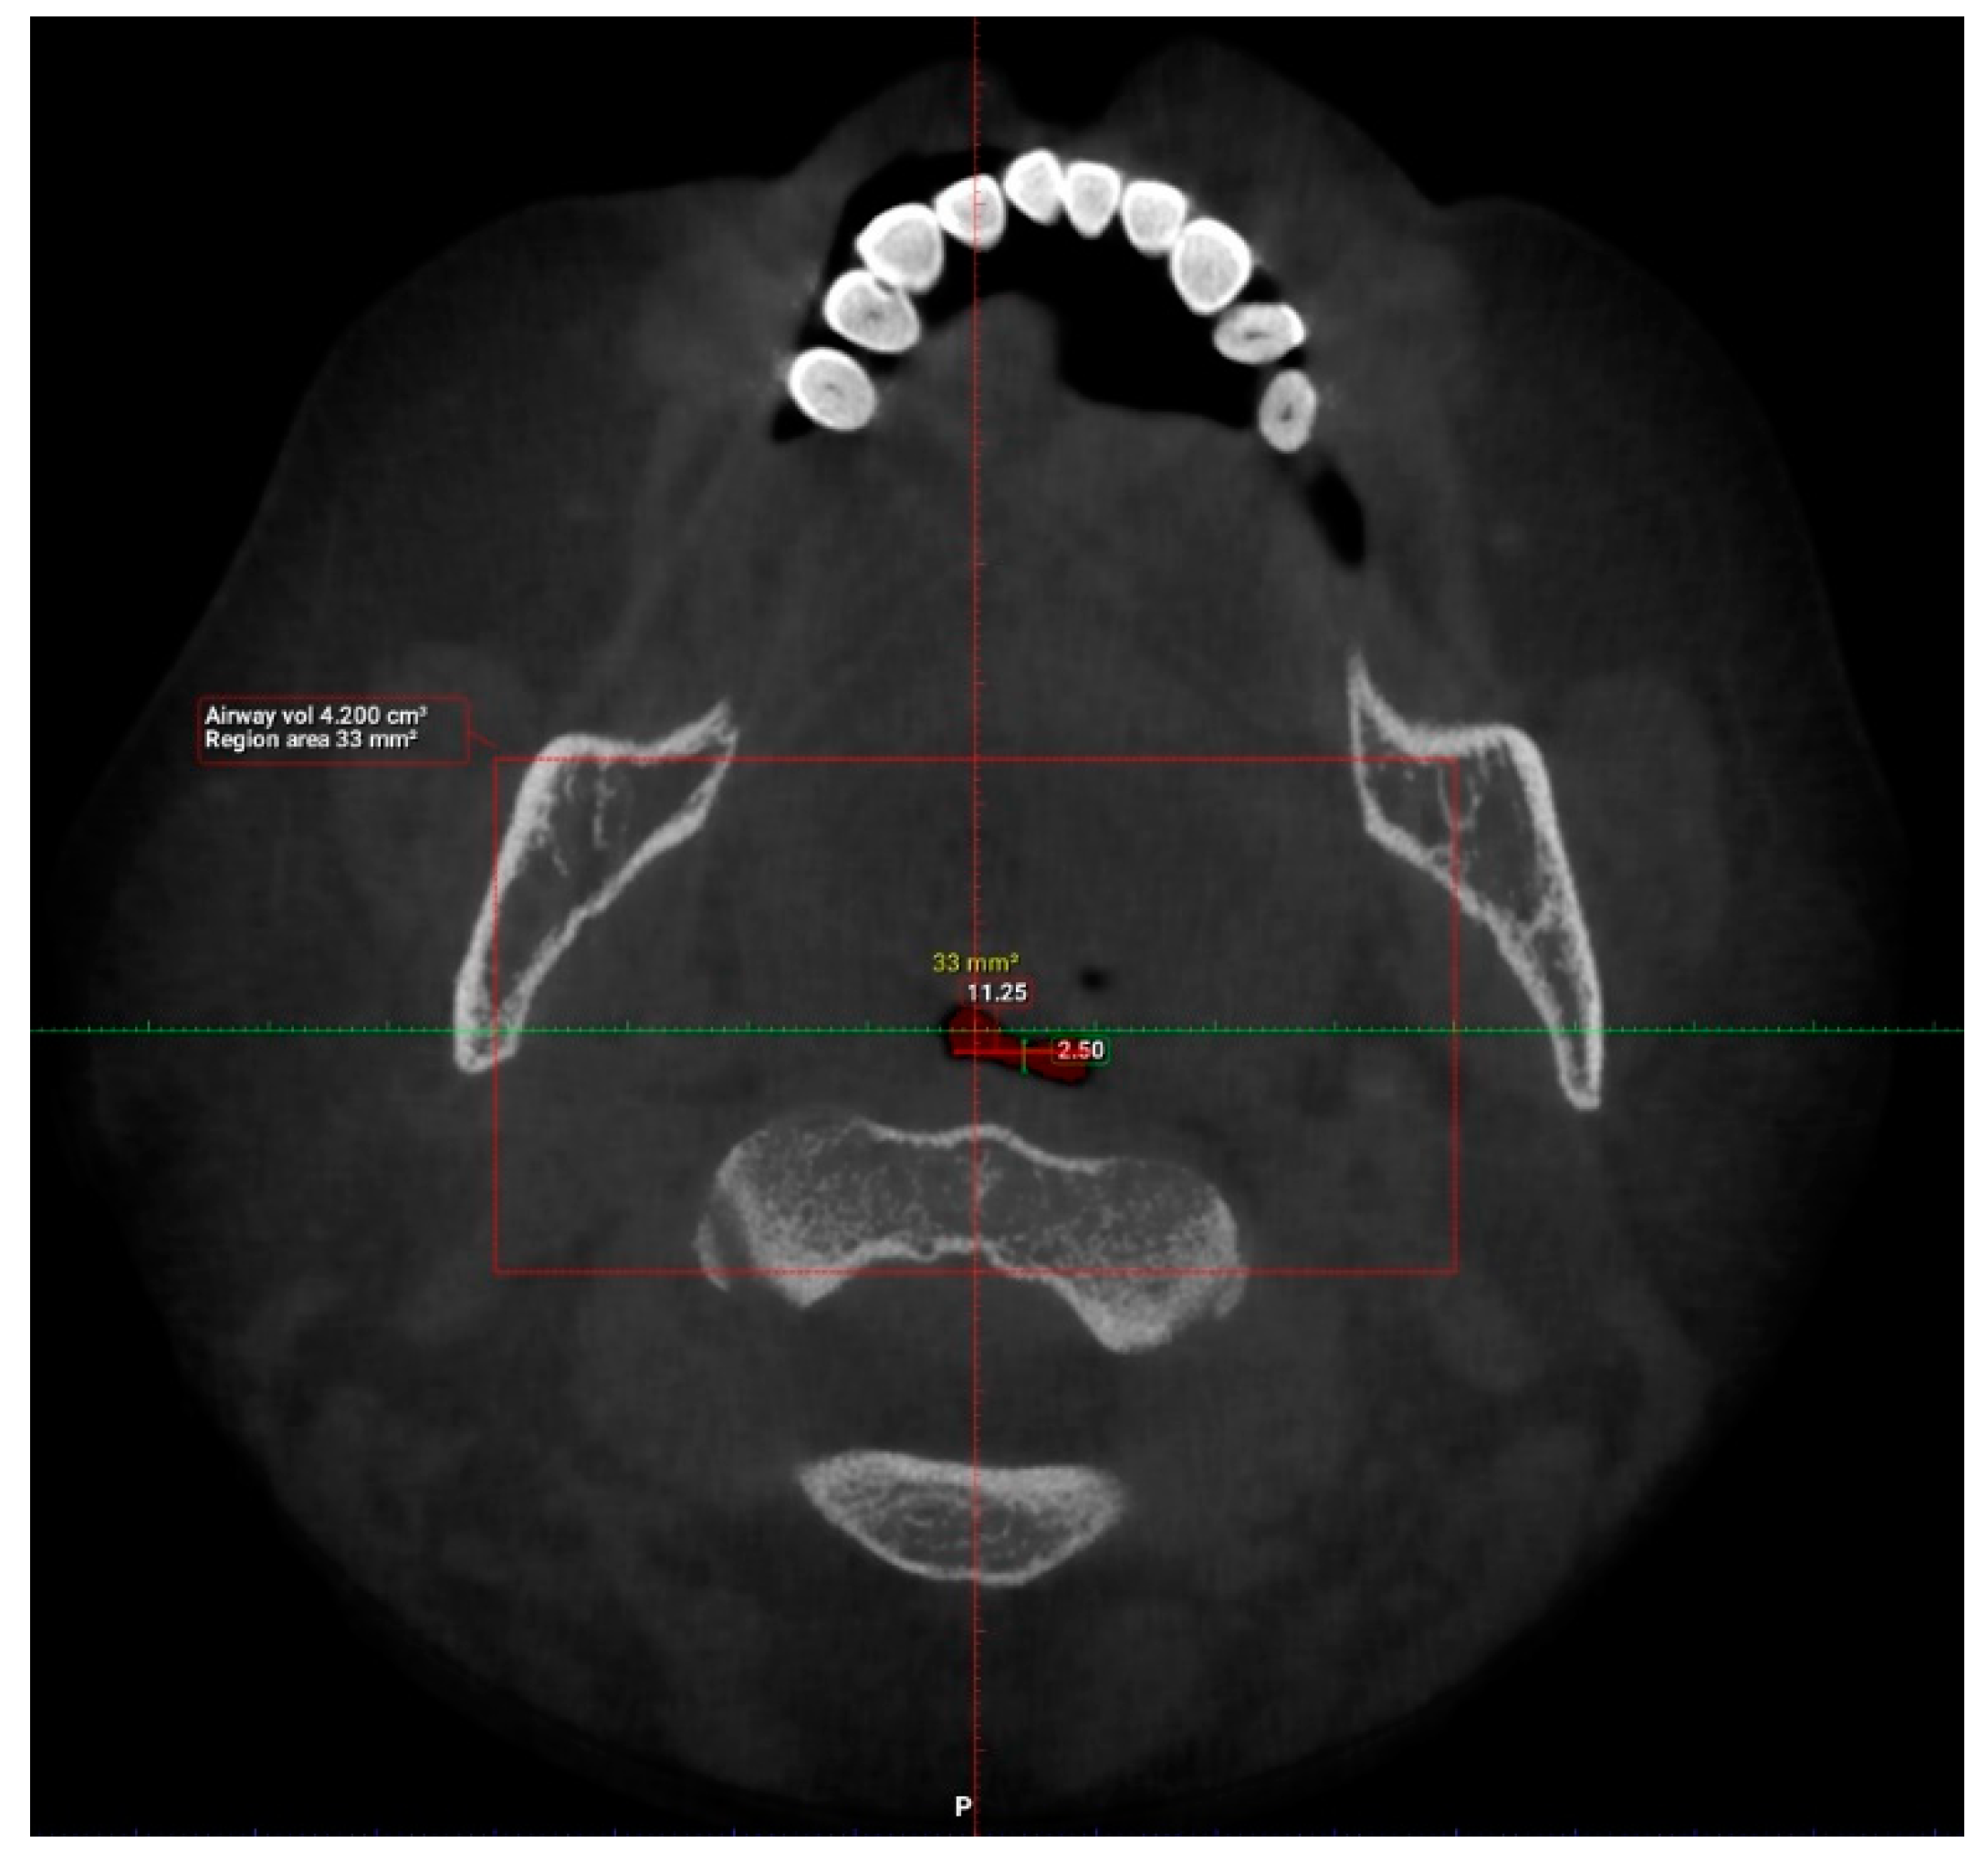

| Antero-posterior (mm) | 101 | 1.00 | 14.50 | 6.44 | 3.19 |

| Width (mm) | 101 | 8.00 | 37.00 | 21.69 | 6.54 |